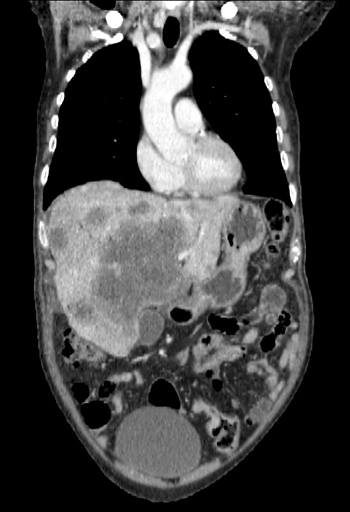

Imagen 1: Compresión medular con aplastamiento de D3 y masa de partes blandas asociada.